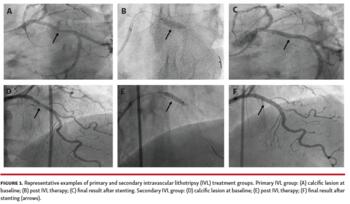

Subgroup analysis. The patient cohort were further divided into 3 subgroups: (1) the primary IVL subgroup, in which patients had IVL to de novo lesions; (2) the secondary IVL subgroup, in which patients had IVL after failure of non-compliant, high-pressure balloon dilation; and (3) the tertiary IVL subgroup, in which patients had IVL to underexpanded stents.

IVL procedural characteristics. IVL-related procedural characteristics are presented in Table 3. Pre-IVL and post-IVL balloon dilation were done in the majority of lesions (82% and 78%, respectively). Modified balloons, like scoring balloon (22%), cutting balloon (6%), and ultra-high pressure OPN balloon (22%), were also used in specific cases for lesion preparation and optimal stent expansion. Rotational atherectomy was performed in 1 patient before IVL. The majority of lesions (96%) were treated with drug-eluting stent and 2 in-stent restenosis lesions were treated with drug-coated balloon. Representative examples of IVL treatment are presented in Figures 1 and 2.